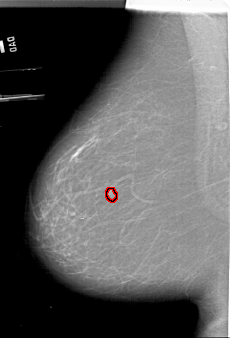

A_1450_1.LEFT_MLO

LEFT_MLO LINES 6421 PIXELS_PER_LINE 4366 BITS_PER_PIXEL 12 RESOLUTION 43.5 OVERLAY

FILE: A_1450_1.LEFT_MLO.OVERLAY

TOTAL_ABNORMALITIES 1

ABNORMALITY 1

LESION_TYPE MASS SHAPE LOBULATED MARGINS CIRCUMSCRIBED

ASSESSMENT 3

SUBTLETY 3

PATHOLOGY BENIGN

TOTAL_OUTLINES 1

BOUNDARY